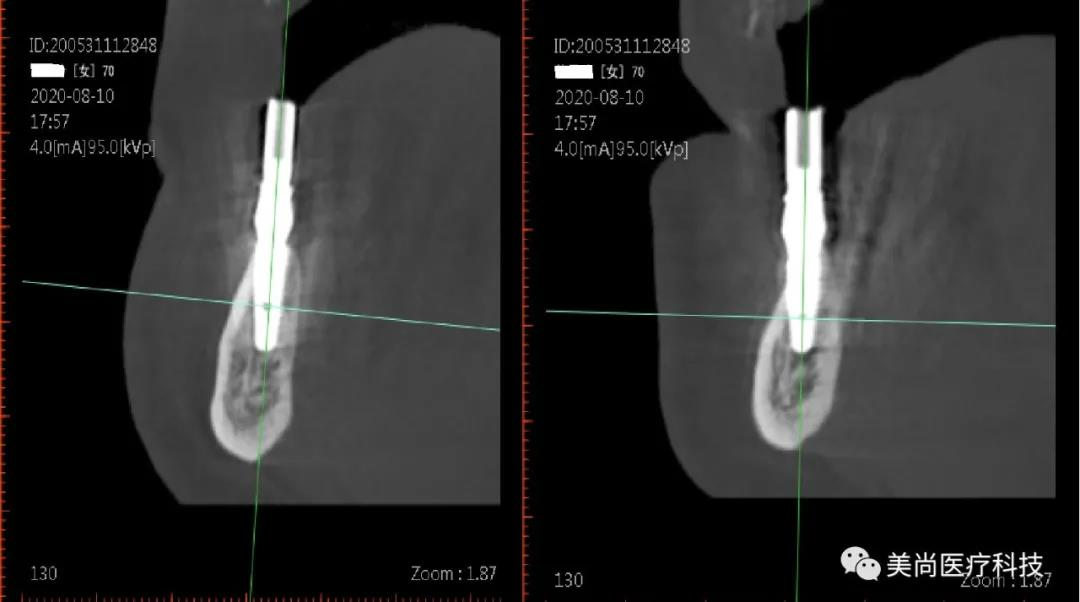

32、42可用骨宽度6mm,可用骨高度10mm;

34、44可用骨宽度6mm,可用骨高度11.5mm。

在32、42处植入3.5*10mm植体各一颗,植入扭矩约35n.cm;

在34、44处植入4.0*11.5mm植体各一颗,植入扭矩约40n.cm。